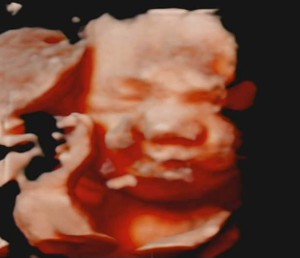

30주 입체초음파입니다 :)

이레IYRAE

2025-08-21